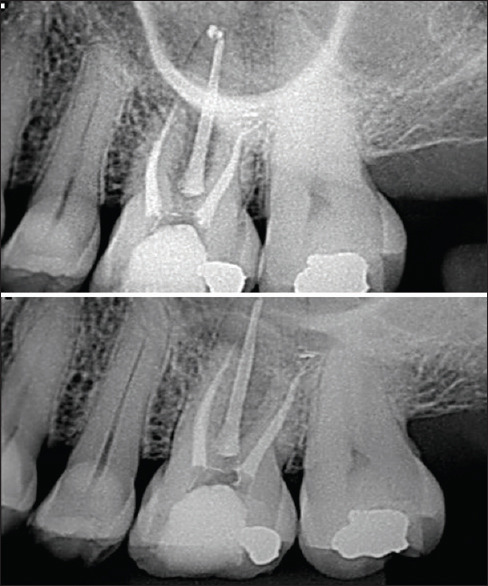

牙齿分叉缺陷的牙周治疗是具有挑战性的,因为该区域的复杂解剖结构。切除技术,如根切除,可以有效地治疗牙齿缺损,如果有适当的指示,可以导致令人满意的存活率和良好的预后。本报告描述了使用根切除结合再生手术治疗上磨牙II级分叉缺陷。再生过程包括使用冻干骨移植物结合使用胶原膜和结缔组织移植物。24个月的随访证明了治疗的成功,临床附着水平增加,探测袋深度减少,断层图像显示新硬膜层的形成。一个健康和稳定的牙周组织可以通过正确的应用更保守的技术来保护牙齿。

Periodontal treatment of teeth with furcation defects is challenging due to the complex anatomy of the area. Resective techniques, such as root resection, may be effective in managing teeth with this defect if appropriately indicated and can lead to satisfactory survival rates associated with a favorable prognosis. This report describes the treatment of a Class II furcation defect in an upper molar using root resection combined with regenerative procedures. The regenerative procedure involved the use of a lyophilized bone graft combined with the use of a collagen membrane and a connective tissue graft. The 24-month follow-up demonstrated the success of the therapy, with a gain in clinical attachment level, a reduction in probing pocket depth, and a tomographic image showing the formation of new lamina dura. A healthy and stable periodontium can be achieved through the correct application of more conservative techniques aimed at preserving the dental element.